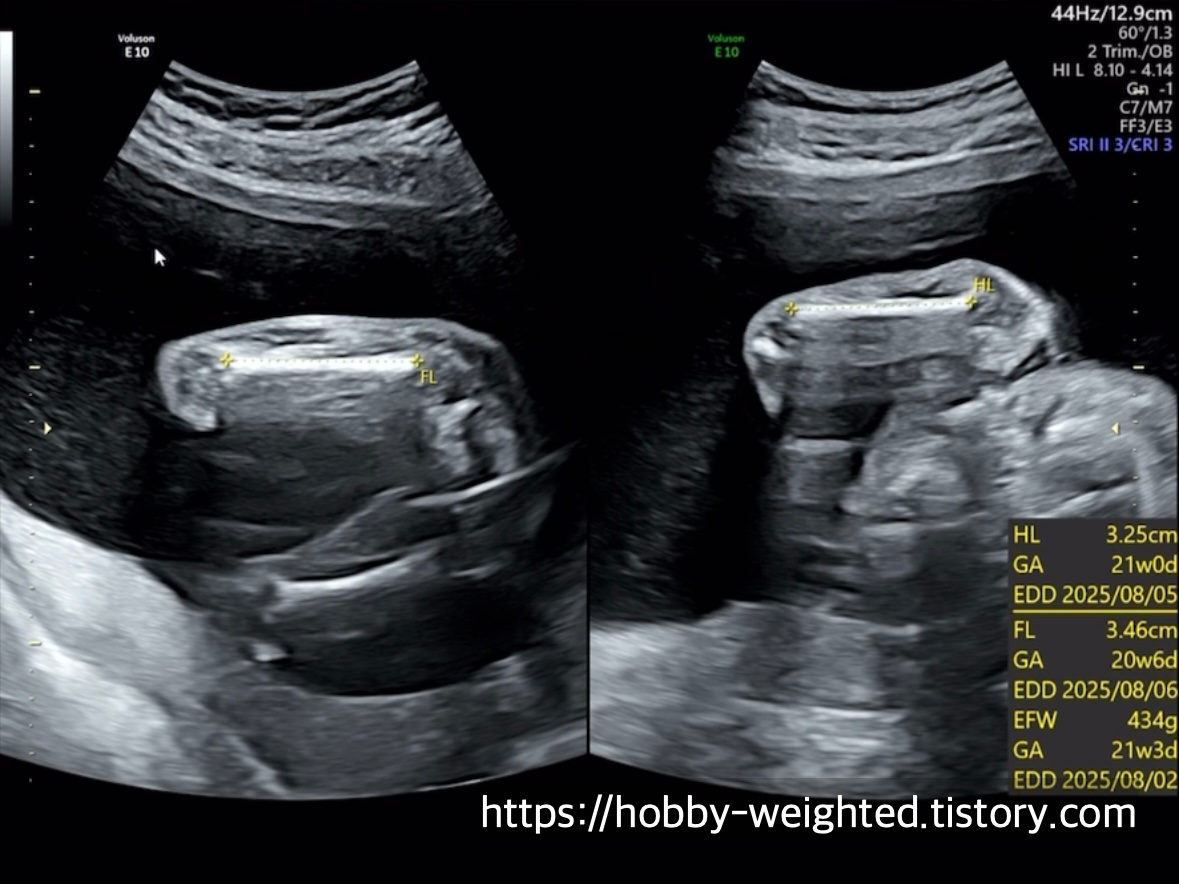

기본 정보(머리둘레, 몸통둘레, 허벅지뼈 길이)

· FL(Femur Length): 대퇴골(허벅지뼈) 길이

· EFW(Estimated Fetal Weight): 태아 예상 체중

· GA(Gestational Age): 임신 주수

· EDD(Estimated Due Date): 예상 분만일

전체적인 성장 정도를 판단한다(434g이다 ㅋㅋㅋ 귀여워).